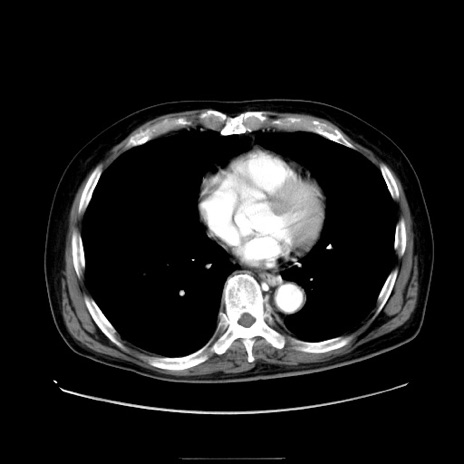

症例30(横断像)

【症例】80歳代男性

【主訴】臍周囲痛

【現病歴】約6時間前から臍下部痛が出現。次第に腹部膨隆・背部痛も生じてきたため来院。背部痛の場所は変化しない。

【身体所見】意識清明、BT 36.3℃、BP  131/87mmHg、P 87bpm、SpO2 100%(RA)、臍周囲自発痛・圧痛あり、反跳痛なし、自発痛部位に一致して板状硬あり、腹部膨隆、腸雑音減弱、CVA tenderness両側陰性。

【データ】WBC 19600、CRP 0.33